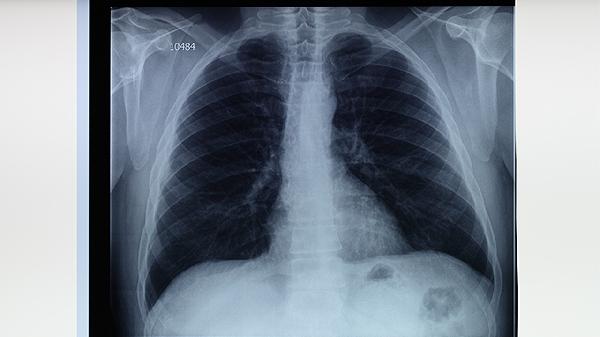

肺结核的病因主要有结核分枝杆菌感染、免疫力低下、长期接触传染源、营养不良以及合并慢性疾病等。肺结核是由结核分枝杆菌引起的慢性传染病,主要通过呼吸道传播,当人体免疫力下降时容易发病。